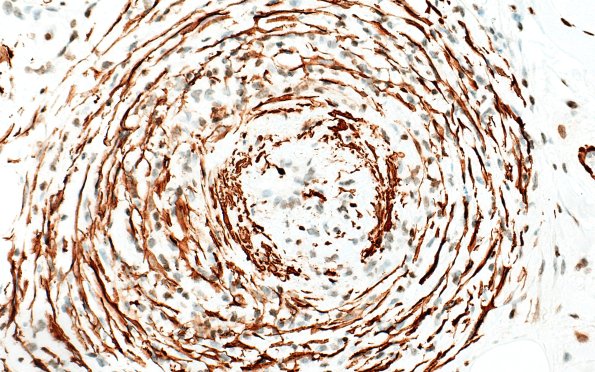

Washington University Experience | PERIPHERAL NEUROPATHY | 11 VASCULITIS - VASCULOPATHY | 3 Vasculitis - NOS | 31B4 Vasculitis (Case 31) SMA 40X

Random sampling of vasculitic elements showing loss of their wall structure. (SMA IHC)